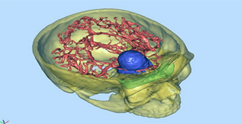

1) MARCO ESTEREOTAXIA: Marcación estereotáctica para lesiones profundas , craneotomias guiada por estereotaxia y/o asistidas por Neuronavegación. (Incluirá el equipo)

VI. CIRUGIA FUNCIONAL , ESTEREOTAXIA Y EPILEPSIA

Se prestará la asistencia para la alternativa terapéutica en casos de enfermedades refractarias a tto médico, cirugía en casos de movimientos